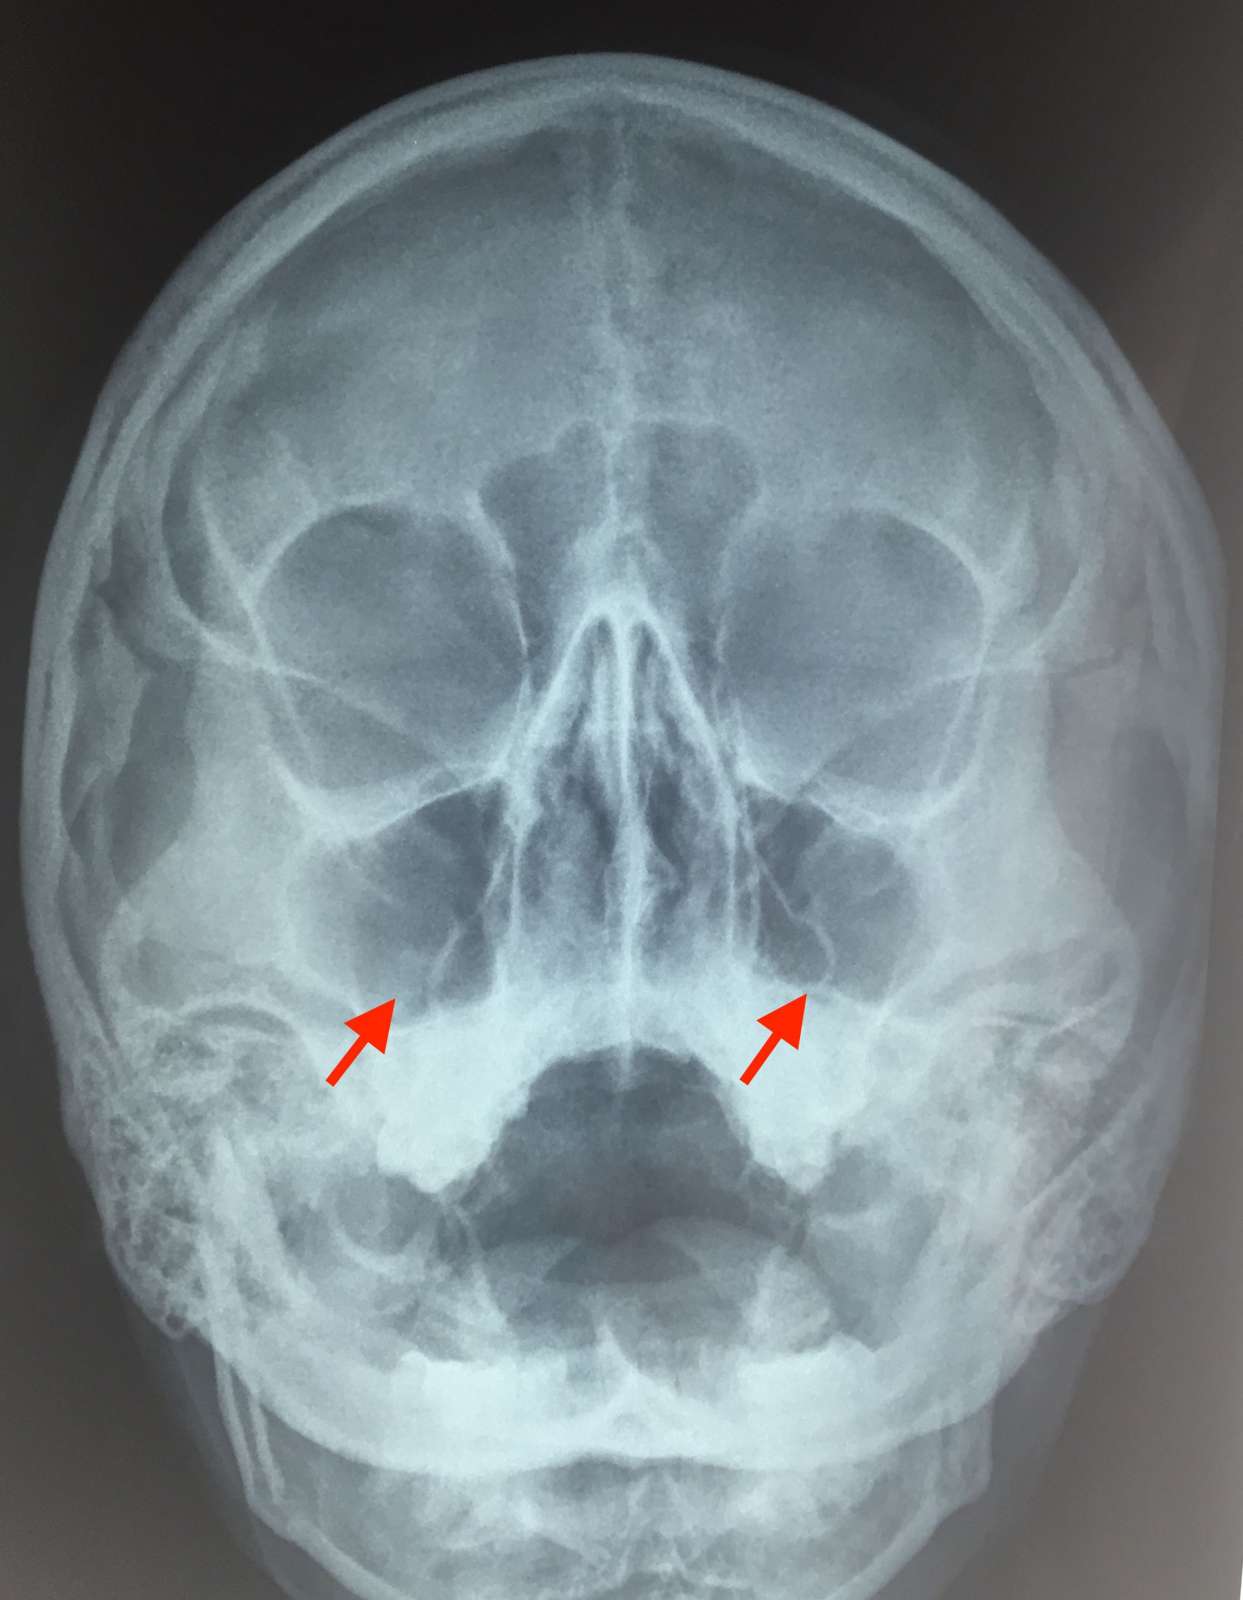

Діагноз виставляється на підставі скарг пацієнта, даних зовнішнього огляду (визначається рефлекторне розширення шкірних судин подглазничной області), огляду слизової носової порожнини (запалення, набряк, гнійні виділення з отвору пазухи). На рентгенограмі гайморової пазухи виявляється затемнення. При недостатній інформативності інших методів дослідження виконується пункція гайморової пазухи.

Рентгенограма придаткових пазух носа. Рівень «рідина-газ» у лівої в/щелепної пазусі